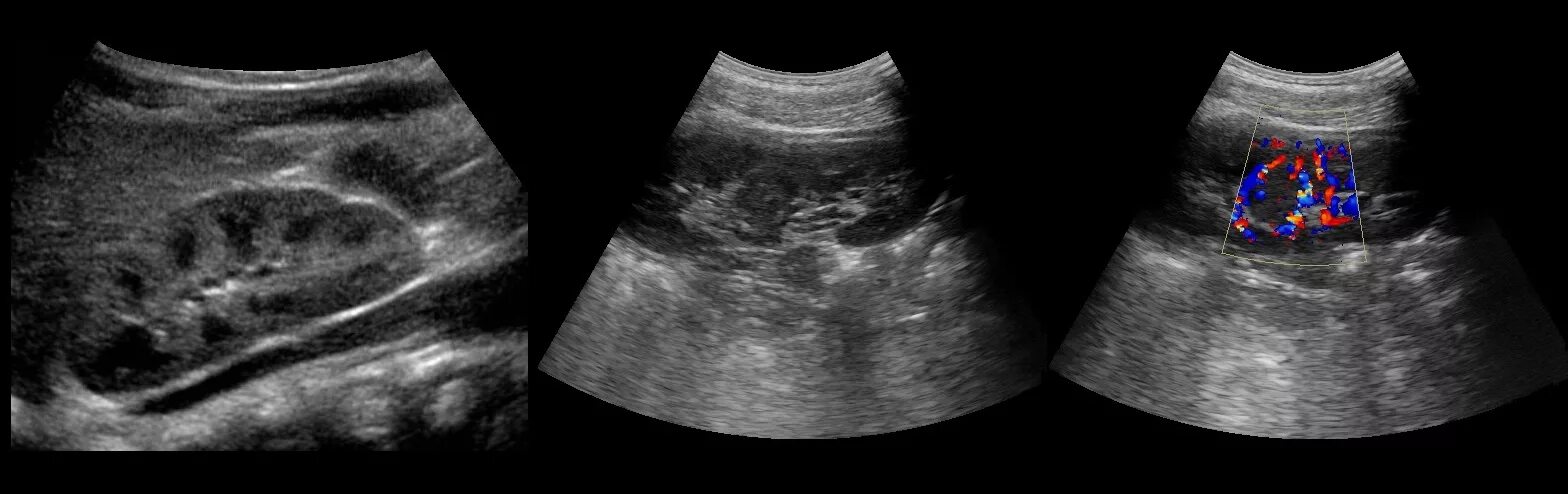

Диффузно неоднородное изменение синусов почек